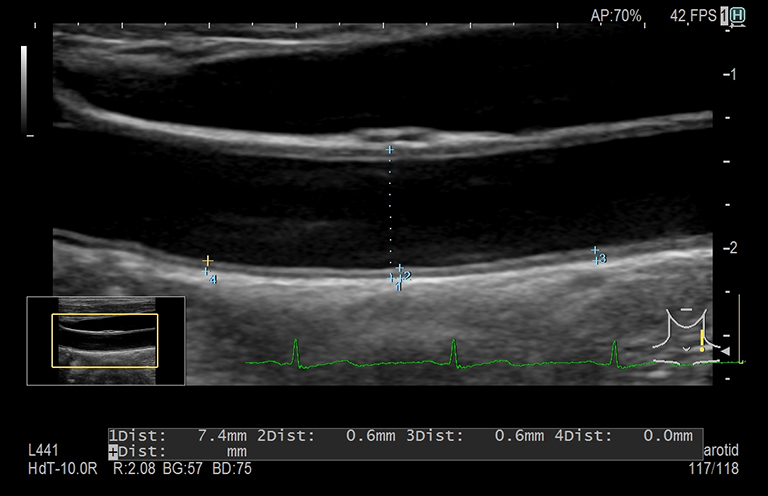

Aplicación: Vascular

Función/análisis: IMT automático

Comentarios: Arteria carótida